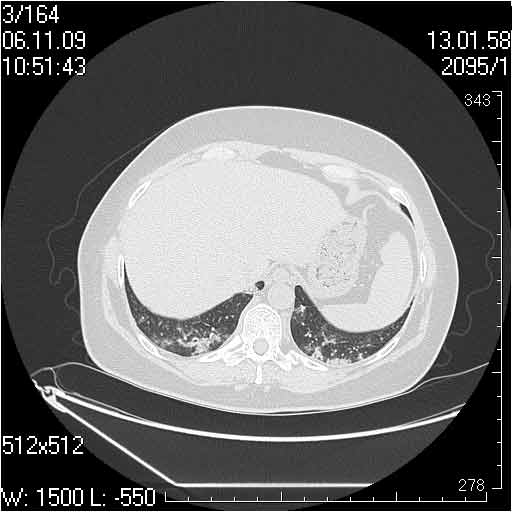

Случай №3

Женщина 51 год

Случай 3:смешанные изменения; подходят для интерстициальной пневмонии, тактика аналогична случаю 1.